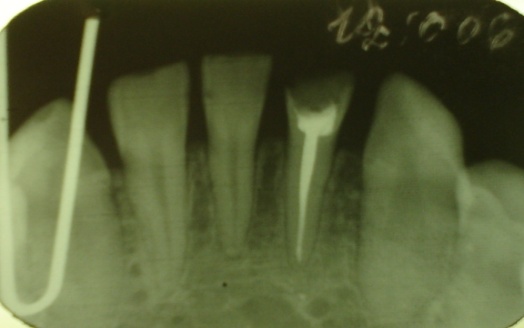

| Рис. 18. Нависающий край пломбы у 46 зуба. Деструкция межзубной перегородки у корня 46 зуба, костный карман. Высота межзубной перегородки у 46 зуба снижена на 1/3 длины корня. Рис. 19. Локализованный пародонтит в области 44,45,46 из-за отсутствия контактных пунктов. Снижение высоты межзубных перегородок на 1/3. Расширение периодонтальной щели 45. Остеопороз. Рис. 20. Снижение межзубной перегородки между 31 и 41 зубами на 2/3 длины корня, остеопороз. Локализованный пародонтит тяжелой степени. Рис. 21. Глубокое резцовое перекрытие. Мелкое преддверие полости рта. Высота межзубных перегородок на уровне эмалево-цементной границы. Деструкция кортикальных пластинок вершин межзубных перегородок. Расширение периодонтальной щели в боковых отделах. Остеопороз межзубных перегородок. |